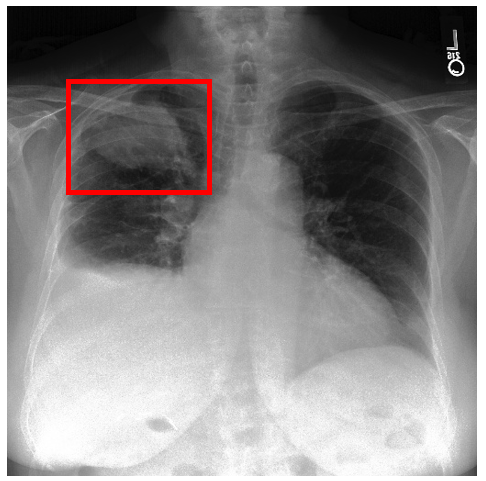

3.3 Interpretability

Post-Hoc Comparisons. We compare our concept-based explanations to post-hoc XAI techniques LIME and SHAP, applied to the baseline InceptionV3 model. The image explanations generated by these techniques disagree with each other and the medical ground truth. We show an example of this observation in Figure 7, where both techniques fail to capture the large mass in the X-ray, and highlight irrelevant regions such as areas outside of the lung as incorrectly important to the classification decision. In contrast, our approach correctly identifies the presence of a mass. More examples are shown in Figure 10.

Refer to caption

(a) Ground Truth

(b) LIME

(c) SHAP

(d) CXR-LLaVA Generated Report

(e) Our Approach

Figure 7: Example of our explanation approach outperforming LIME, SHAP and CXR-LLaVA. Ground truth (a) is a “Large right upper zone mass". LIME (b) and SHAP (c) fail to capture the mass in the X-ray. Most important image regions are bounded by yellow for LIME, and shown in more vibrant green for SHAP. CXR-LLaVA (d) generates a report which wrongly describes the image as non-cancerous. Our approach (e) correctly identifies the presence of a mass.

(a) Ground Truth 1

(b) Ground Truth 2

(c) Ground Truth 3

(d) Ground Truth 4

(e) LIME 1

(f) LIME 2

(g) LIME 3

(h) LIME 4

(i) SHAP 1

(j) SHAP 2

(k) SHAP 3

(l) SHAP 4

Figure 10: Examples of LIME and SHAP explanations failing to capture the medical ground truth of a cancerous chest X-ray, while also generating conflicting explanations. Ground truth (a,b,c,d) is shown as red squares. Most important regions are bounded by yellow for LIME (e,f,g,h) and shown as more vibrant green for SHAP (i,j,k,l).